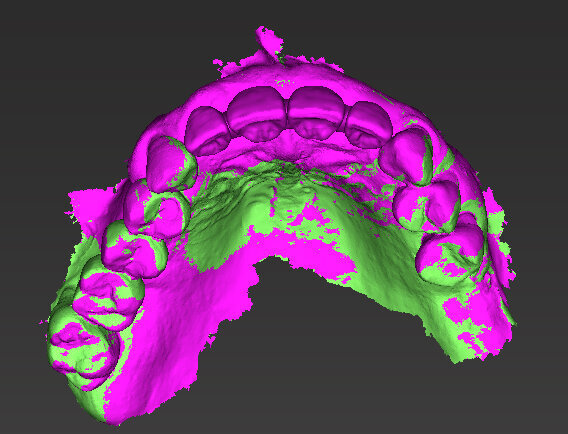

Il piano di trattamento prevede l’estrazione degli elementi dentali, l’inserimento di due impianti e la realizzazione di una protesi fissa di quattro elementi. Il problema da gestire è quello della fase provvisoria. Non è ipotizzabile una protesi mobile e quindi programmiamo di inserire subito dopo l’intervento un provvisorio immediato. Questo ci consente di condizionare da subito i tessuti periimplantari e anche le zone dei ponti. Si rileva un’impronta digitale (Figg. 5, 6), e la programmazione degli impianti viene effettuata con un software di chirurgia guidata (Fig. 7) e la posizione degli impianti nello spazio biologico e nello spazio protesico viene fatta sulla base di una ceratura diagnostica (Figg. 8, 9). Inseriamo gli impianti virtuali nell’osso disponibile (Figg. 10-13) e in relazione all’aspetto protesico correggiamo l’asse di inclinazione degli impianti con componenti secondarie angolate a 17° (Figg. 14, 15). Questo ci consentirà di realizzare una protesi avvitata con i fori situati nella zona palatale.

Fig. 9 - Visione occlusale ceratura.